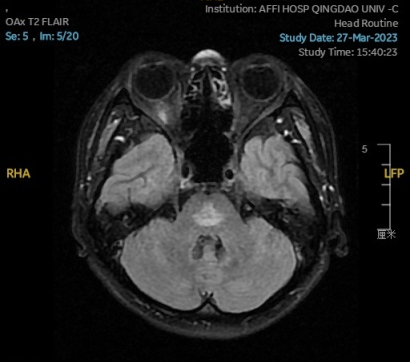

2023.02.09颅脑MR平扫示双侧基底节区及桥脑异常信号,考虑渗透性神经脱髓鞘综合征可能,脑桥部病灶较前范围增大,请结合临床,见图2。

图2 2023.02.09颅脑MR成像示双侧基底节区及桥脑见对称性片样长T1长T2信号,FLAIR呈高信号,较2023-01-18MR所示脑桥病灶范围增大。脑室、脑池、脑沟、脑裂未见明显异常。中线结构居中。